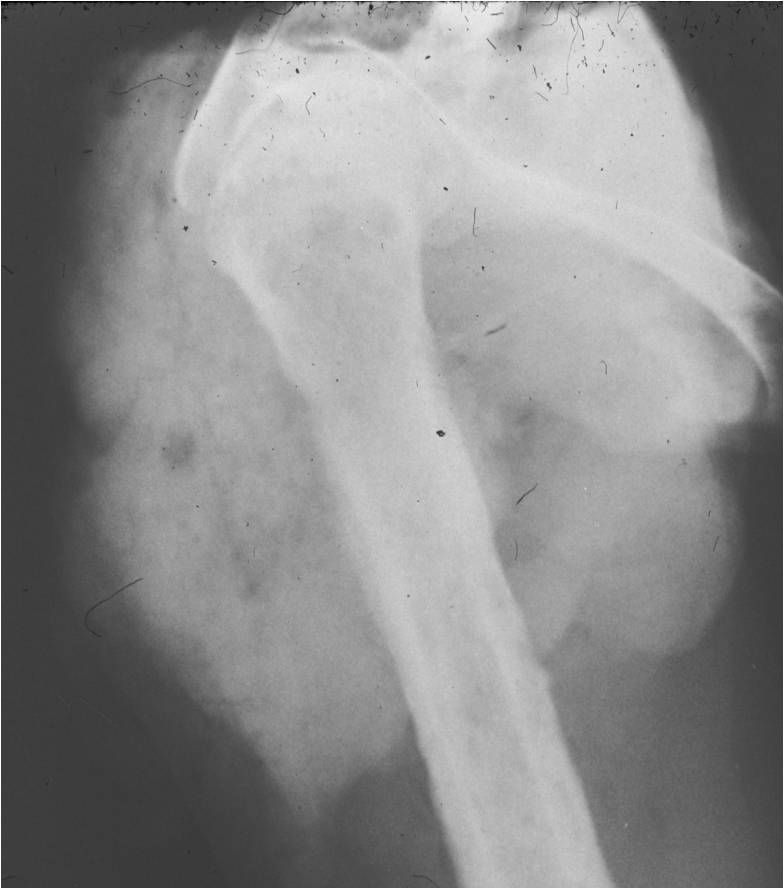

Radiographic Presentation

- Aggressive motheaten to permeative lesion

- Indistinct border in most cases

- Osseous destruction with a soft tissue component

- Chondroid matrix calcification may be present (60-70% of cases)

- Soft tissue mass